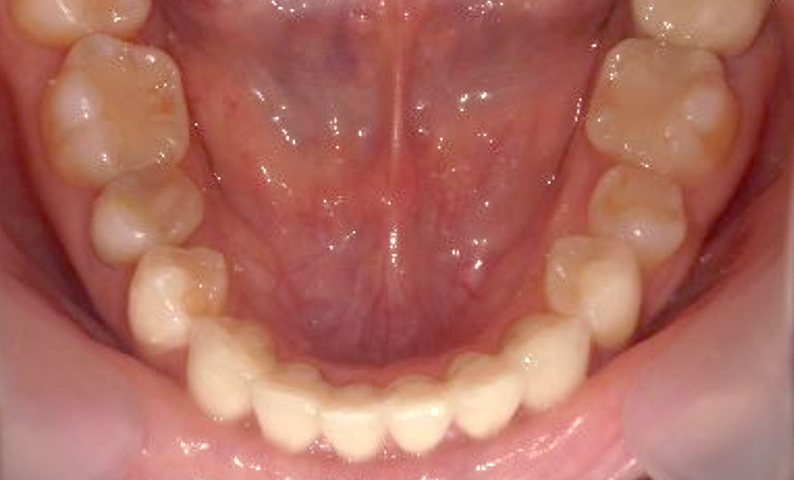

症例_003 上下顎の部分矯正

治療期間:12ヶ月金額:54万円+税男性八重歯前歯のガタガタ